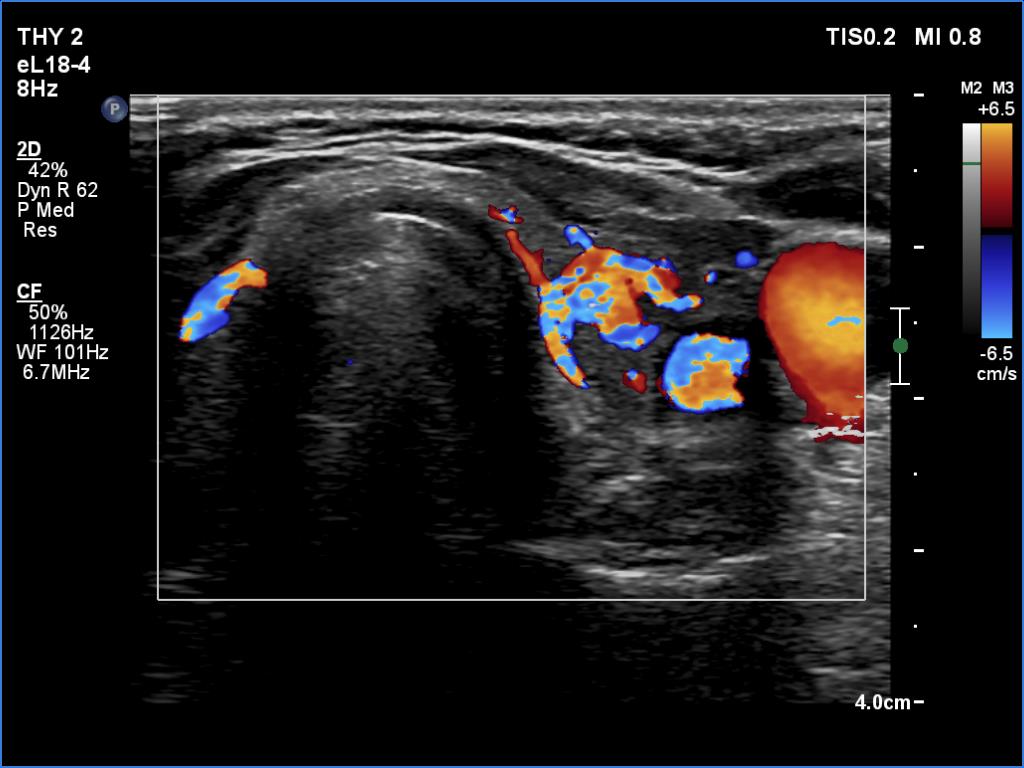

Subacute granulomatous thyroiditis - case 1514

Second examination 3 months later (ultrasonographic picture 8)

Left lobe, transverse scan, color Doppler mode. The vascularity is increased.